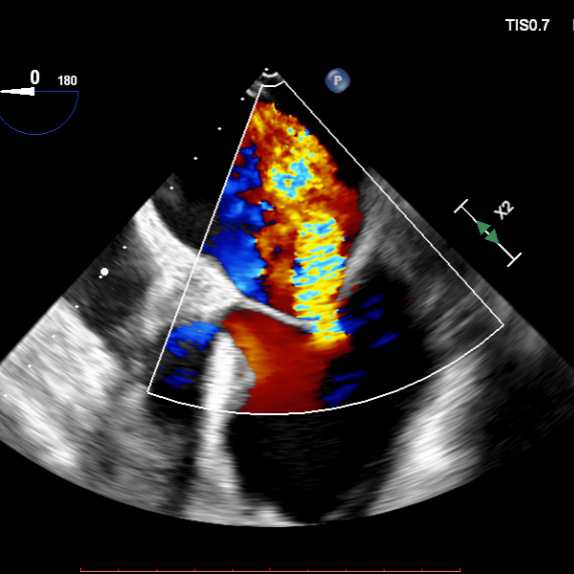

1.四腔心切面和二腔心切面可见左室高侧壁室壁瘤形成,二尖瓣瓣叶脱垂伴重度反流。

3D MV View: 二尖瓣前后瓣叶对合不全,A2/P2稍偏1区可见未闭间隙。PISIA主要来源于A2/P2区域。